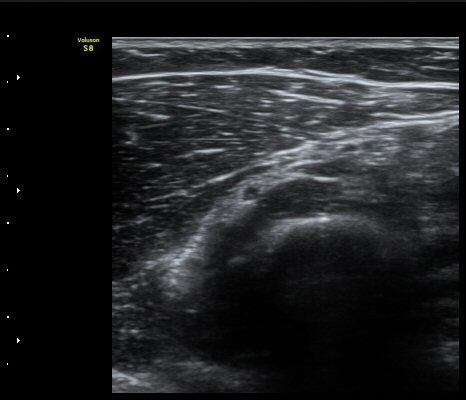

[ÆÈ²ÞÄ¡] Å״Ͻº¿¤º¸¿ì(¿Ü»ó°ú¿°)¿¡ µ¿¹ÝµÈ ¿ä°ñ½Å°æ Èİñ°£ºÐÁö º´Áõ 2

ÃÊÀ½ÆÄ °Ë»ç